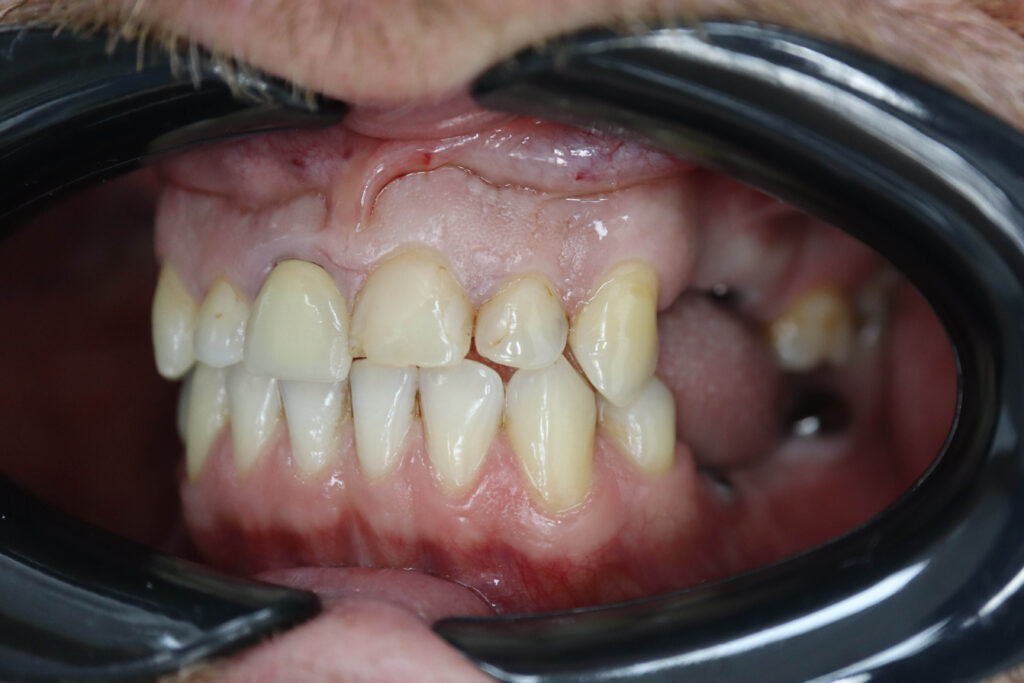

Ситуация до лечения

Пациент обратился с жалобами на эстетические недостатки.

Диагноз: Частичная адентия

Ситуация до лечения Бутримович